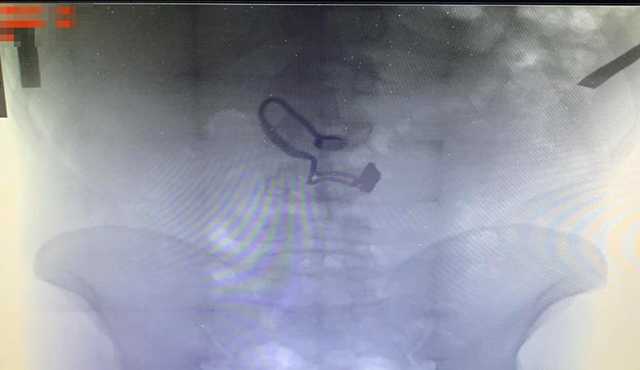

Украшение обнаружили на рентген снимке. Столичные жители задержали мужчину, который отобрал у 73-летней прохожей кошелек, сорвал с ее шеи цепочку и проглотил ее.

Во время медосмотра на рентген снимке задержанного врачи обнаружили украшение. По данному факту начато уголовное производство по части второй статьи 186 (грабеж) Уголовного кодекса Украины. Фигуранту объявили о подозрении. За содеянное ему грозит до шести лет лишения свободы.